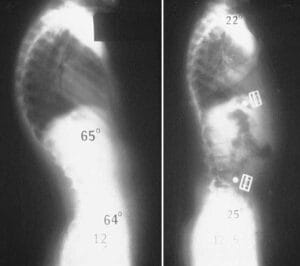

While the thoracic spine naturally curves between 20 and 45 degrees, certain postural or structural abnormalities can increase this curvature beyond normal limits. Known medically as hyperkyphosis when it exceeds 50 degrees, this excessive curvature is often simply referred to as kyphosis by doctors to describe the clinical condition resulting in a rounded upper back. The severity of kyphosis can vary. Generally, more pronounced curves lead to a more serious condition. Milder kyphosis may cause minimal discomfort or none at all, while more severe cases can result in noticeable spinal deformity, often producing a visible hump on the upper back.